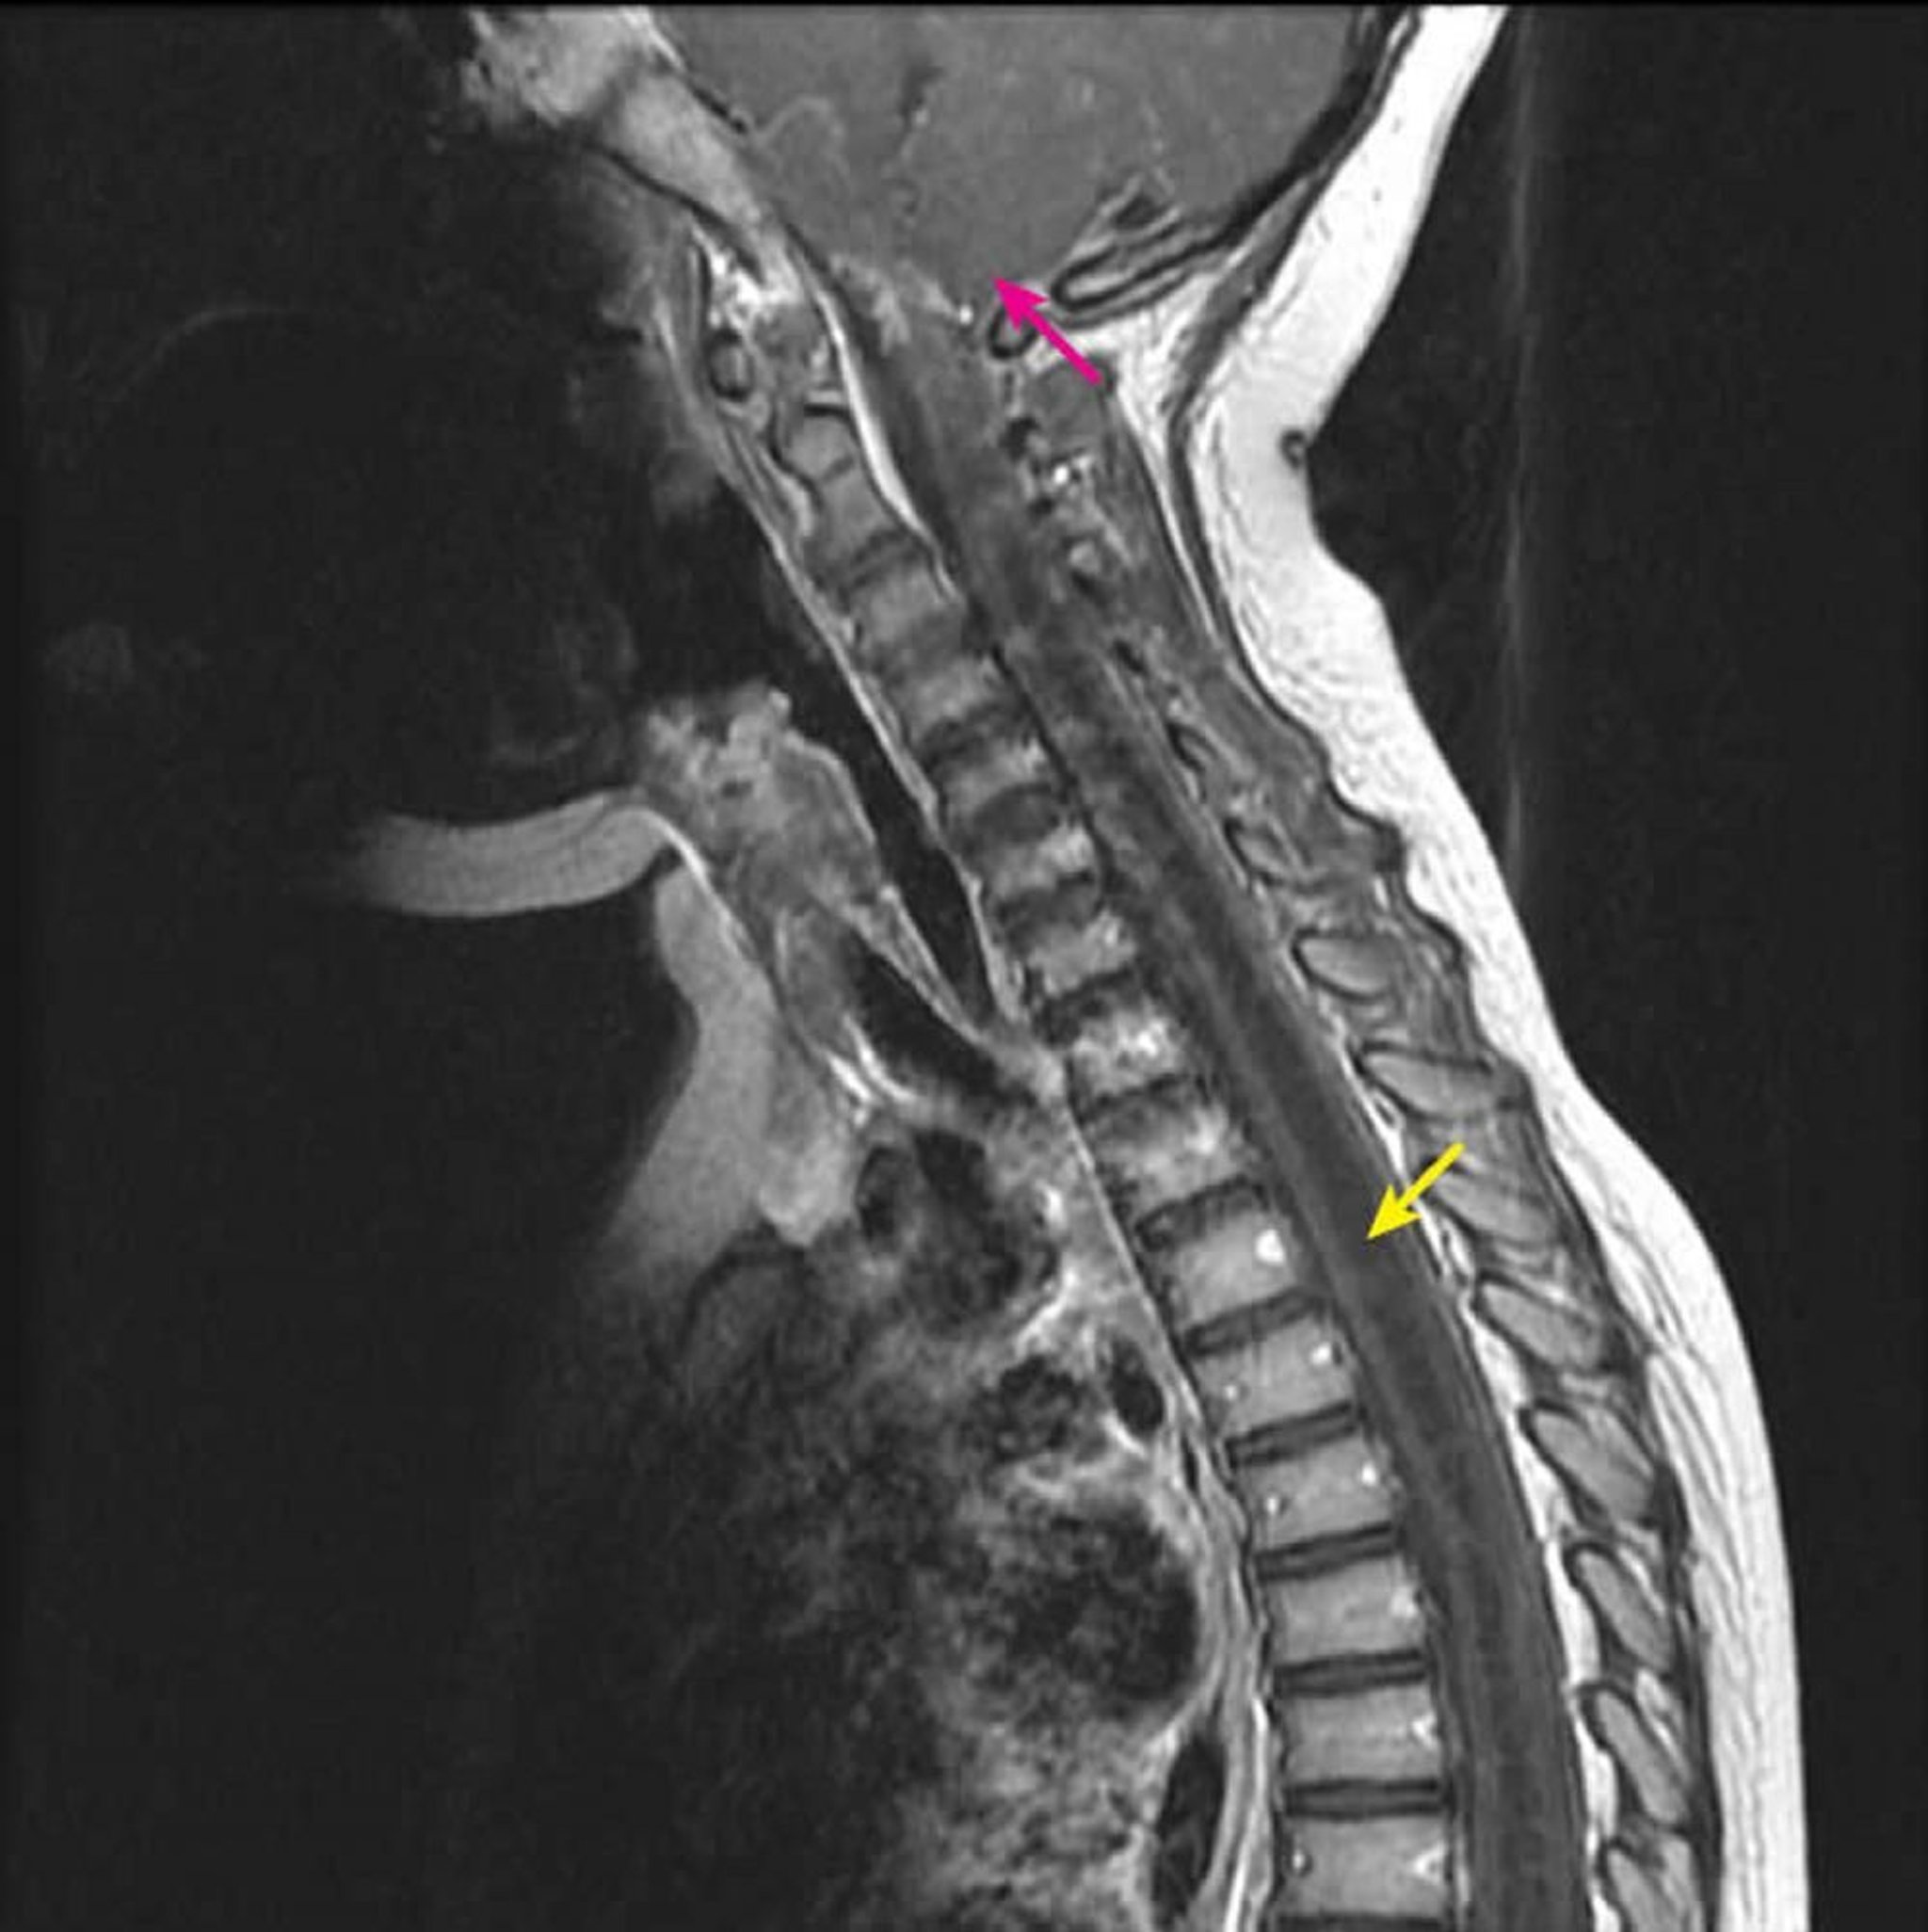

頸胸髄領域のsyringohydromyelia

この造影後のMRI T1強調矢状断では,空洞症に特徴的な脊髄内部の大きな空洞が低信号域として認められる(黄色矢印)。キアリI型形成異常の患児では,空洞がC2-3レベルから下方へと進展する(ピンク矢印)。脊髄空洞症(脊髄中心部以外の空洞)を画像検査でhydromyelia(脊髄中心部の空洞)と鑑別することはできないため,この所見はsyringohydromyeliaと定義される。

Courtesy of John Tsiouris, MD, Division of Neuroradiology, New York–Presbyterian Hospital/Weill Cornell Medical Center.